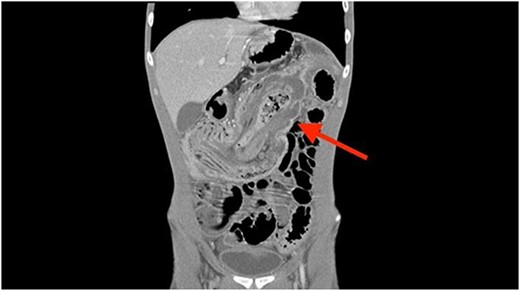

A coronal computed tomography (CT) scan with contrast showed a massive, small bowel to large bowel intussusception involving the majority of the ascending colon and portions of the cecum (Fig. 1). In addition, an axial CT scan showed the classic target sign associated with intussusception (Fig. 2). Due to the patient’s age, a pathologic lead point was suspected, hence surgery was consulted.

Coronal CT scan showing ileocolonic intussusception extending to the sigmoid colon.